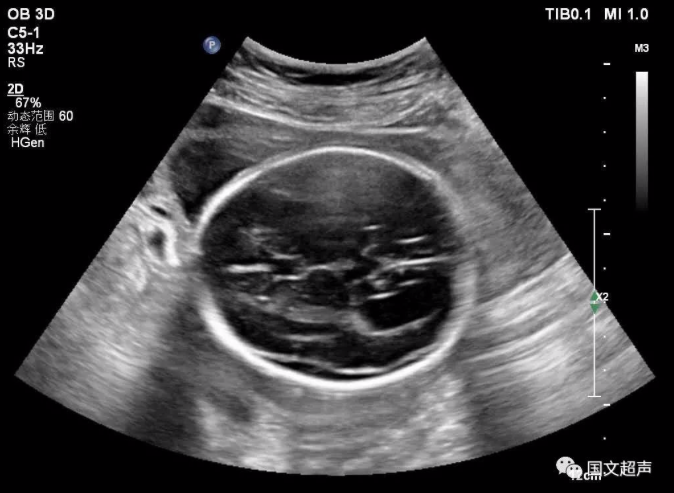

一.關(guān)于側(cè)腦室

側(cè)腦室后角寬度>10mm為腦室輕度擴(kuò)張,而寬度>15mm時即可診斷腦積水,若側(cè)腦室后角寬度<10mm,則應(yīng)考慮其為正常的超聲表現(xiàn)。

大部分輕度腦室擴(kuò)張的胎兒預(yù)后良好,但約有20%的輕度側(cè)腦室擴(kuò)張?zhí)嚎珊喜⒂腥旧w異常、其他顱內(nèi)外異常等問題而出現(xiàn)智力或發(fā)育障礙,甚至在圍生期即死亡。